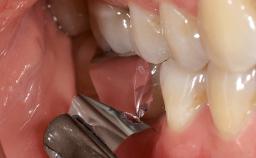

A 37-year-old male patient was referred to the Department of Periodontology at the University of Bern, Switzerland, by a private dentist. Tooth 21 had been lost due to trauma and had been replaced with an implant and a cemented single crown. The tapered-effect tissue-level implant had a diameter of 4.1 mm, a length of 12 mm, and a sandblasted and acid-etched (SLA) surface (Straumann Dental lmplant System; Institut Straumann AG, Basel, Switzerland). The metal-ceramic crown had been cemented permanently, leaving a submucosal gap between the implant shoulder and the crown margin. Absence of marginal bone loss apical to the polished transmucosal neck of the implant could be observed .